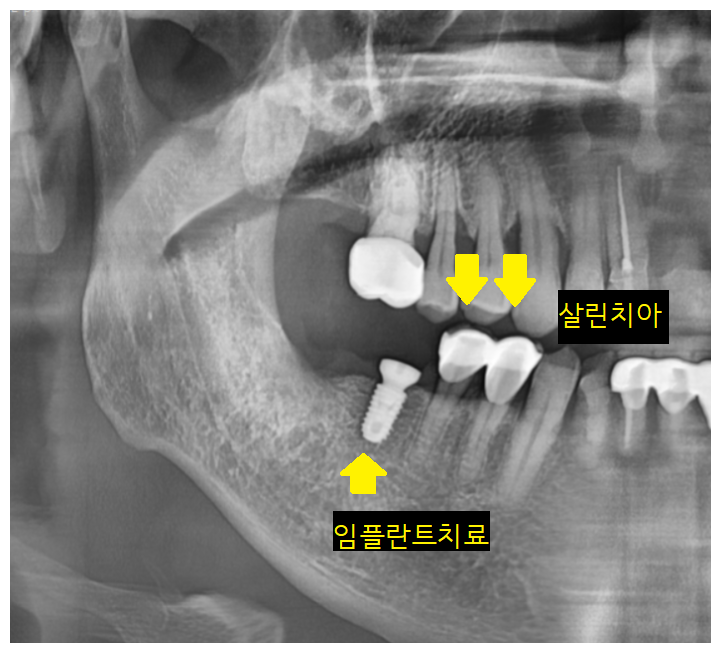

2021.01.05

브릿지 제거 후

고덕역 임플란트 1개 식립하였습니다.

4개 치아가 있던 부분이지만

환자분 상황에 맞춰

1개 임플란트만 진행하였는데요.

위에 어금니 맞닿는 치아가 없어서

2개 임플란트까지는 불필요했습니다.